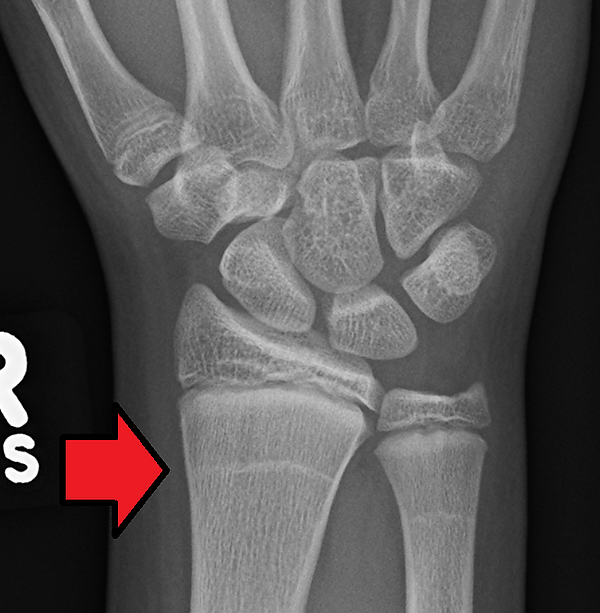

Линии Харриса

Линии Харриса — это индикаторы стресса на скелете, которые образуются из-за недоедания, болезней или других стрессовых факторов в детстве[11][12]. В это время рост костей временно останавливается или замедляется, но минерализация костей продолжается. Как только стресс уменьшился или прекратился, рост костей возобновляется, что приводит к появлению линии повышенной минеральной плотности, которую можно увидеть на рентгенограммах. Если восстановления после стресса не происходит, линия не образуется[8][13].

Амин и др. (2005) изучали распространённость линий Харриса в средневековых популяциях из Берна, Швейцария. Учёные из Университетской больницы Берна собрали рентгенограммы голеней 112 хорошо сохранившихся скелетов, живших в VIII—XV веках. Они также сравнили свои результаты с рентгенограммами 138 живых пациентов из того же географического региона. Они обнаружили признаки линий Харриса у 88 из 112 (80 %) средневековых скелетов и у 28 из 138 (20 %) живых людей. В обеих популяциях линии Харриса были обнаружены в возрасте 2 лет и между 8 и 12 годами. Появление линий Харриса было связано с дегенеративными заболеваниями костей, травмами, остеопорозом, заболеваниями периферических сосудов, рахитом, ревматоидным артритом и костными деформациями. Авторы пришли к выводу, что средневековое население Швейцарии, вероятно, находилось в тяжёлых жизненных условиях и плохом гигиеническом состоянии, а линии Харриса у детей этого населения отражали плохой уход и пренебрежение[14].